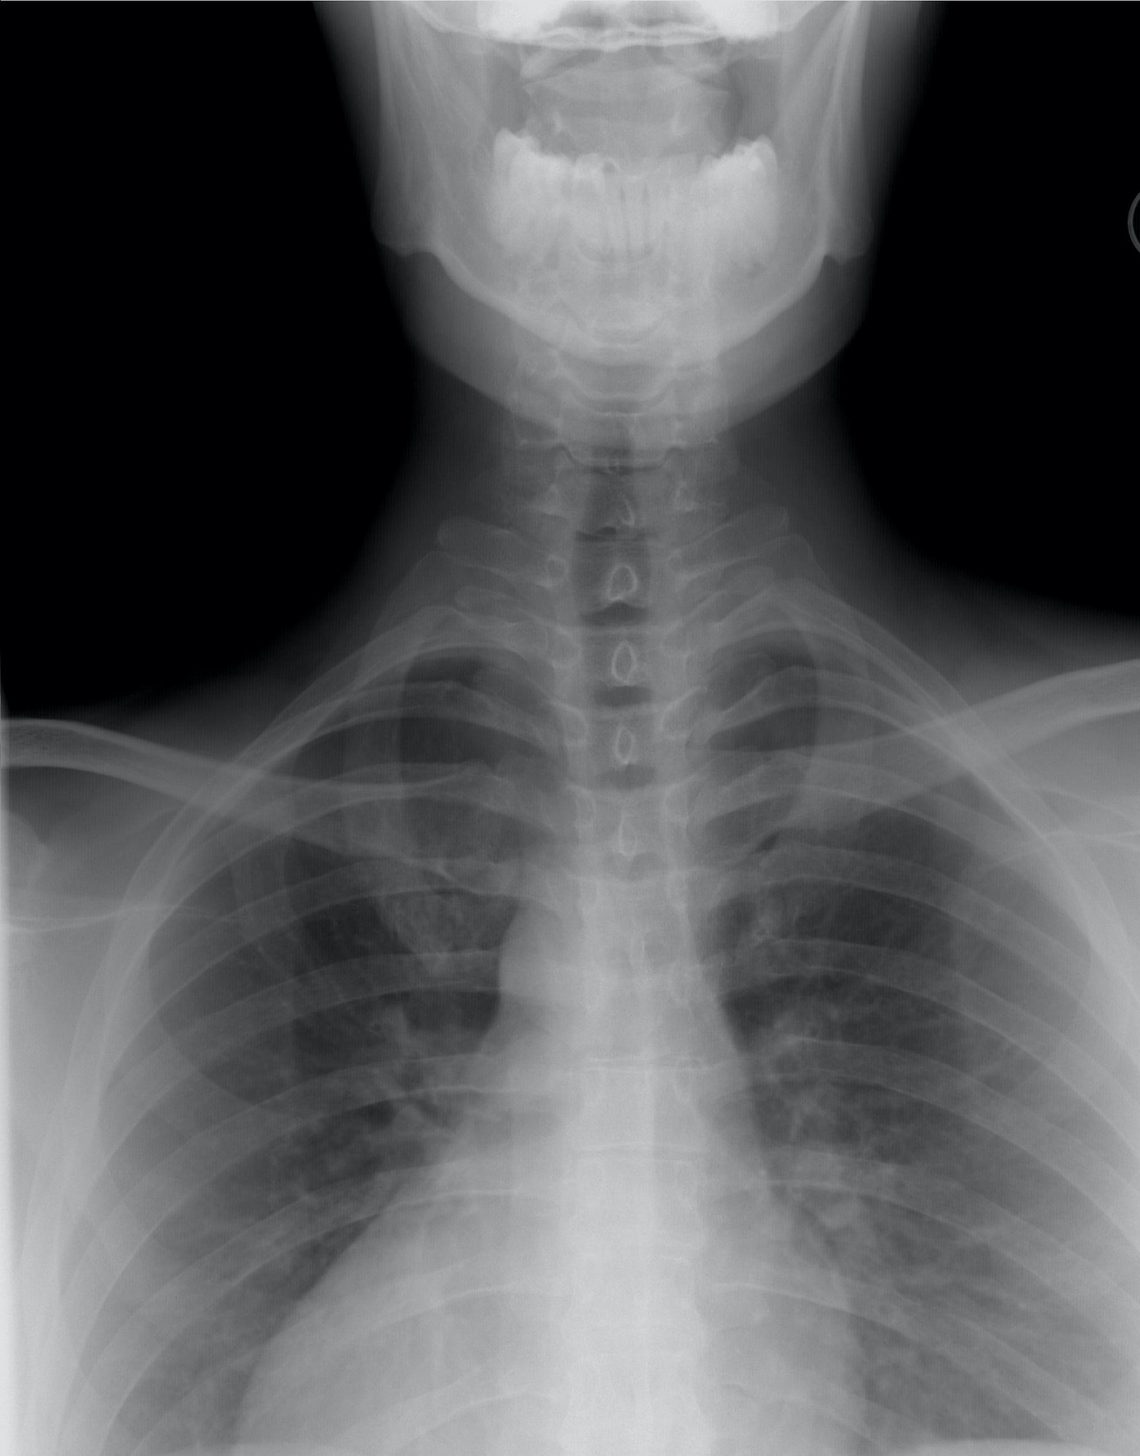

Le pneumologue lui fait passer une radio des poumons. Il lui prescrit un traitement, que Roger va chercher à la pharmacie (ou au supermarché, parce qu’ici les supermarchés font aussi pharmacie).

Changez l’angine de Roger par une grossesse et un accouchement, la jambe cassée par une tumeur bénigne dans le cou et vous comprendrez ce que nous avons vécu pour notre première année aux Etats-Unis. De désillusions en aberrations, je crois que nous sommes passés par toutes les émotions sur le sujet de la santé…